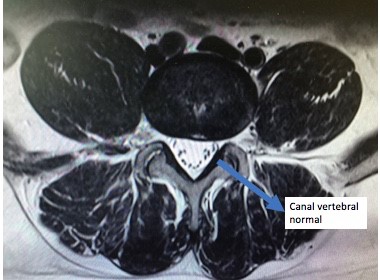

O exame padrão ouro para o diagnóstico da estenose de canal lombar é a ressonância magnética da coluna lombar.

Ressonância magnética com estenose de canal lombar em 2 níveis L3L4 L4L5